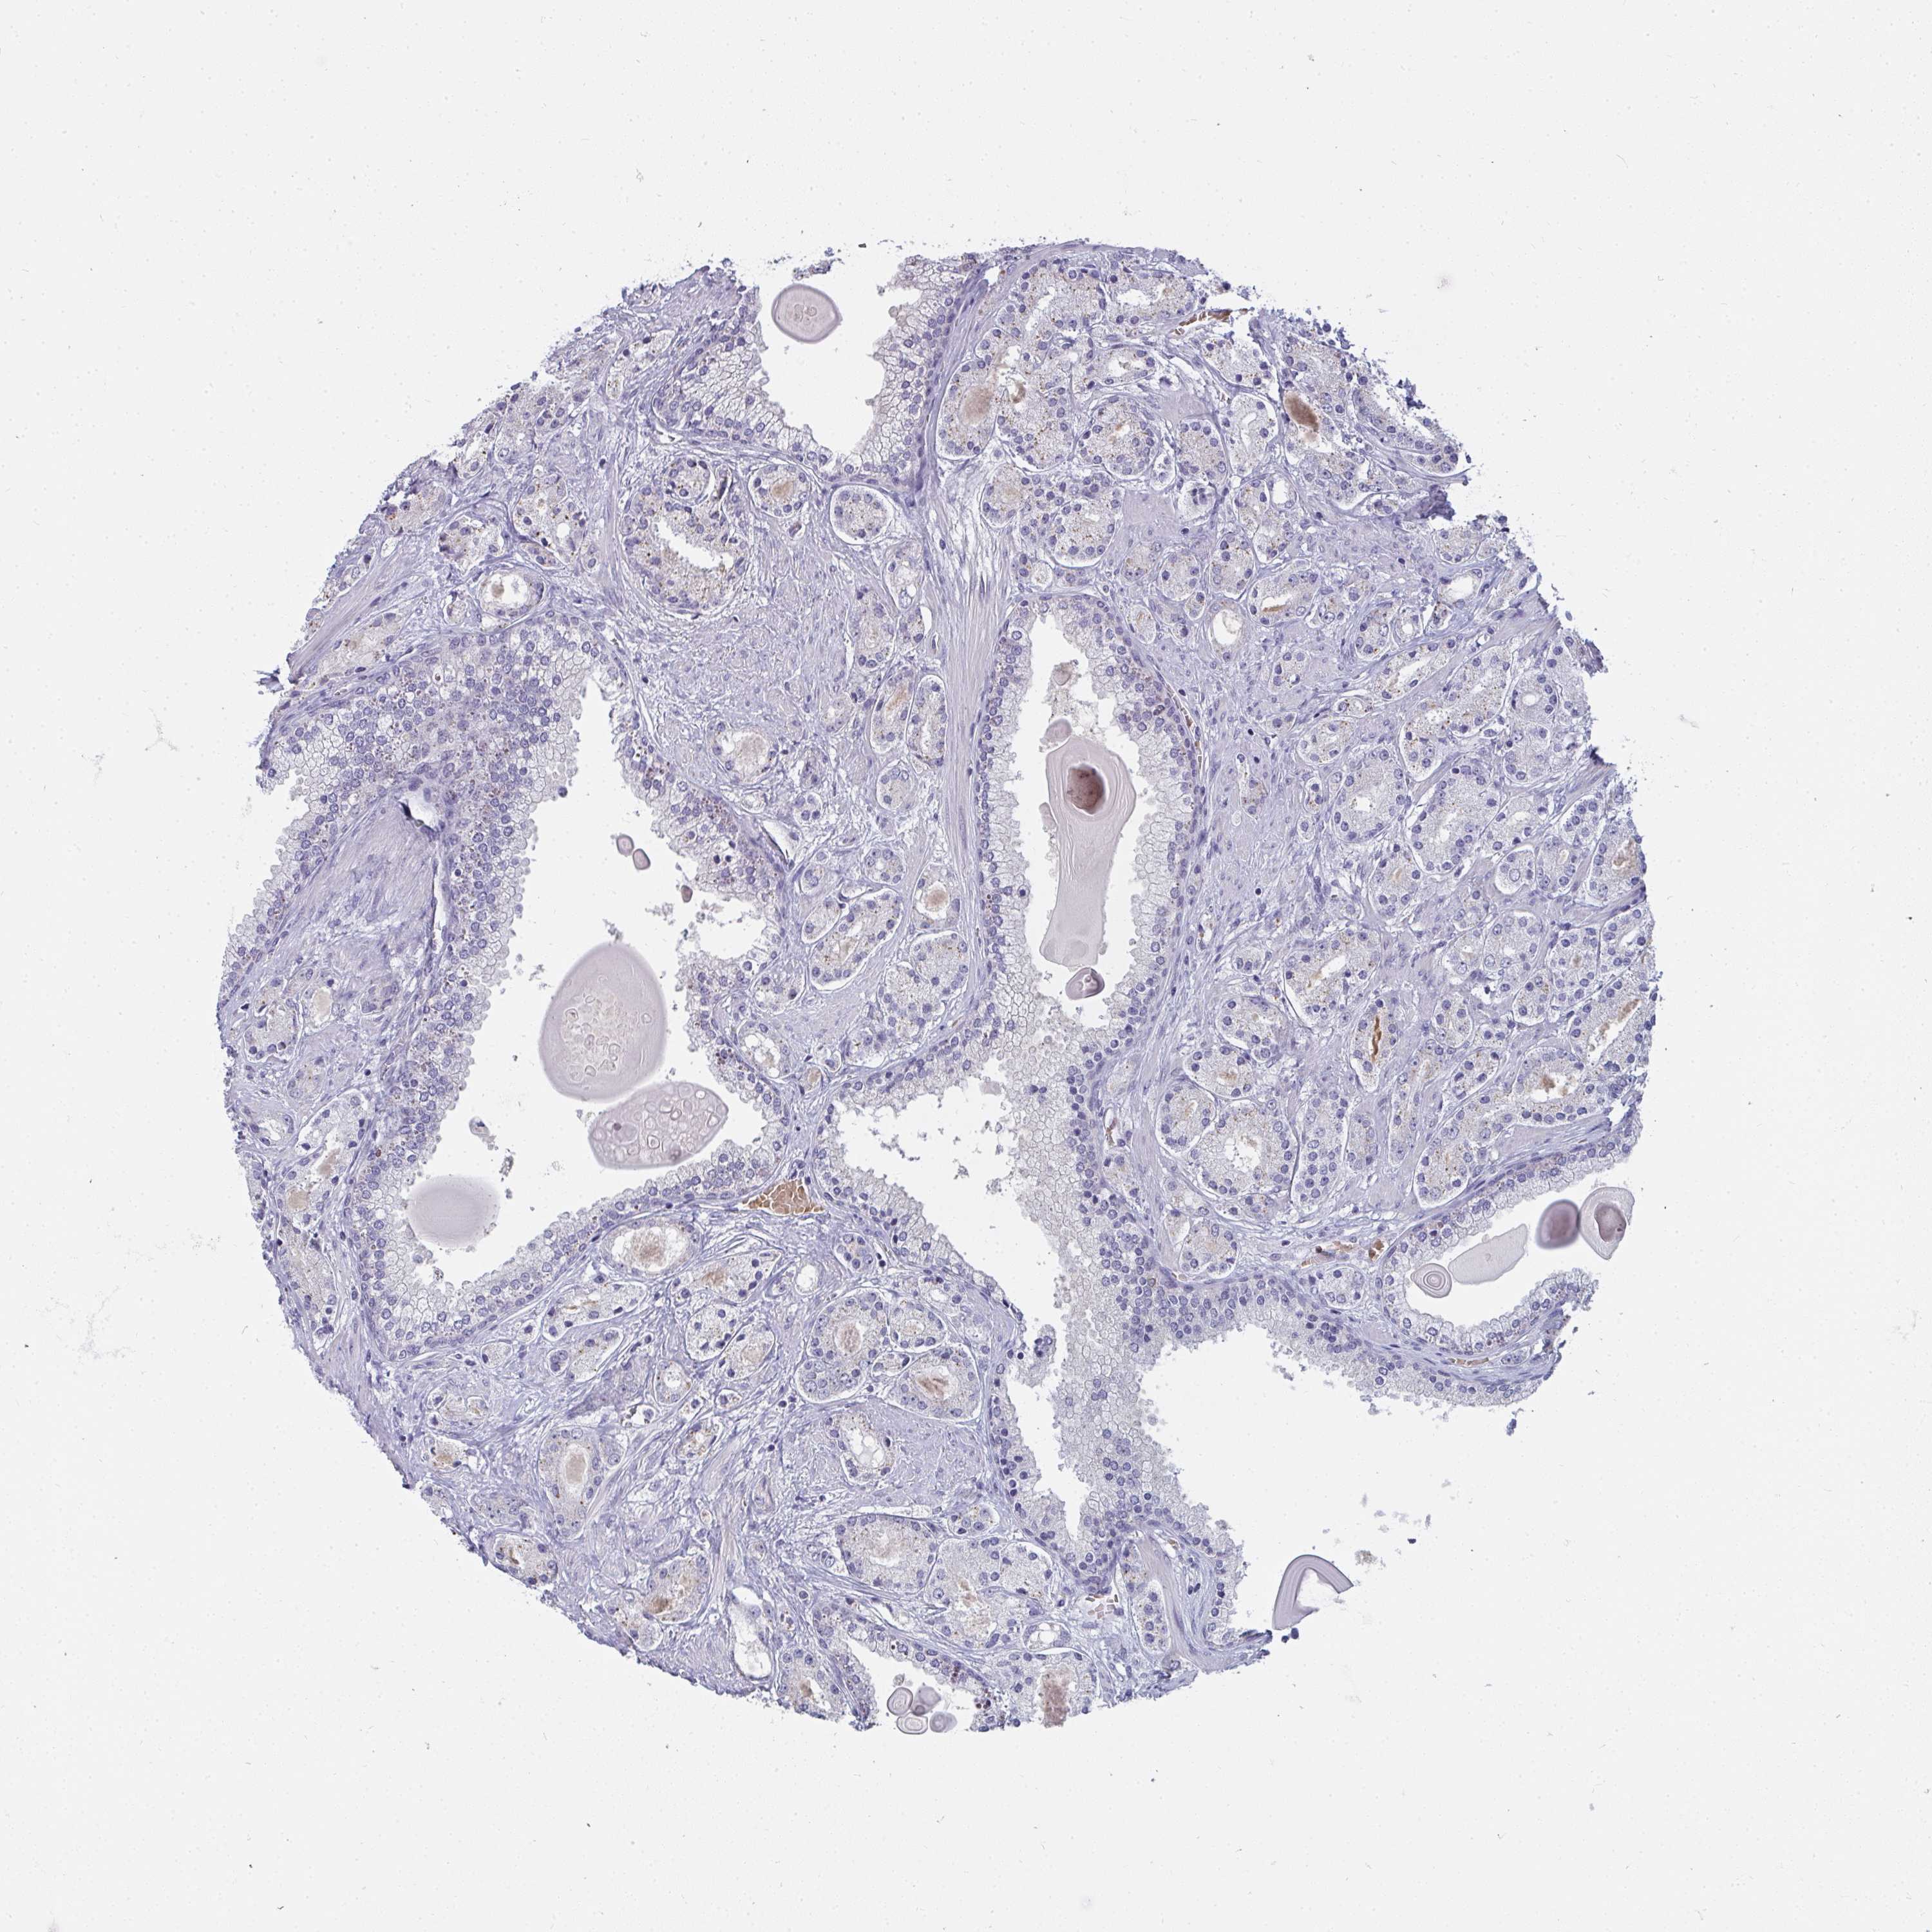

PROSTATE CANCER - Protein expressioni

A mouse-over function shows sample information and annotation data. Click on an image to view it in a full screen mode. Samples can be filtered based on level of antibody staining by selecting one or several of the following categories: high, medium, low and not detected. The assay and annotation is described here.

Antibody stainingi

Antibody staining in the annotated cell types in the current human tissue is reported as not detected, low, medium, or high, based on conventional immunohistochemistry profiling in selected tissues. This score is based on the combination of the staining intensity and fraction of stained cells.

Each image is clickable and will lead to virtual microscopy that enables deeper exploration of all samples and also displays staining intensity scores, fraction scores and subcellular localization as well as patient and tissue information for each sample.

Antibody HPA049911

Antibody CAB010161

Staining

High

Medium

Low

Not detected

Intensity

Strong

Moderate

Weak

Negative

Quantity

>75%

75%-25%

<25%

None

Location

Nuclear

Cytoplasmic/membranous

Cytoplasmic/membranous,nuclear

Adenocarcinoma, High grade

Adenocarcinoma, Low grade

Adenocarcinoma, NOS